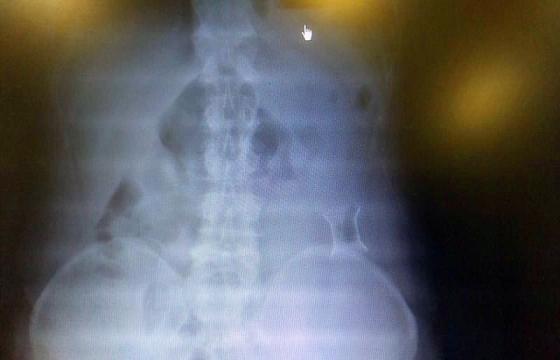

受試患者在結腸端端吻合術中,使用我司新研制產品達到了理想的預期效果?;颊咝g后7天、14天X光片顯影,可降解腸道支架均能按研制設計的預期時間節點保持應有強度,術后21天X光片顯示可降解腸道支架已完全破碎,并排出體外。在整個試驗過程中,病患無任何不良反映,耐受良好。